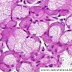

Tráquea de rata (20x)

Observamos el cartílago hialino caracterizado por los condrocitos (Ch) los cuales residen en cápsulas que rodean a las lagunas (Cap, L).

Las lagunas están rodeadas por la matriz interterritorial (*).

El cartílago hialino está rodeado por pericondrio (P).

Técnica: Phosphotungstic acid hematoxylin